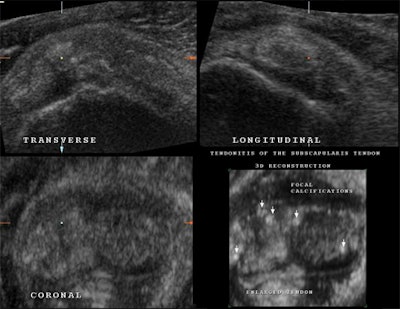

| 3D US and multiplanar imaging of the subscapularis tendon of the rotator cuff in a patient suffering from tendinitis. All three planes show signs of tendon irregularity, enlargement, and dishomogeneity. Multiple focal calcifications are seen in all planes throughout the entire tendon fibers. The use of 3D reconstruction of the same subscapularis tendon demonstrates more clearly the full extent of focal calcifications, tendon irregularity and enlargement, and tendon dishomogeneity. All images courtesy of Dearbhla O'Dwyer and Dr. Stefano Ciatti. |